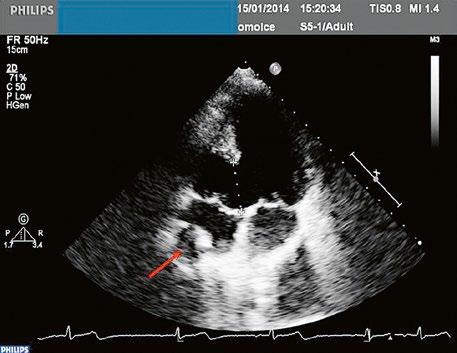

Obr. 45.1 Defekt septa síní typu II v TEE

AO – aorta, DDŽ – ústí dolní duté žíly do pravé síně, defekt septa síní je označen křížky, má předozadní průměr 22 mm, zasahuje blízko zadní stěny levé síně, LS – levá síň, PS – pravá síň

Obr. 45.2 Defekt septa síní typu II v TEE

AO – aorta, ASD – defekt septa síní typu secundum označen šipkou, zelenými křížky je označen malý přední rim k aortě, LS – levá síň, PS – pravá síň